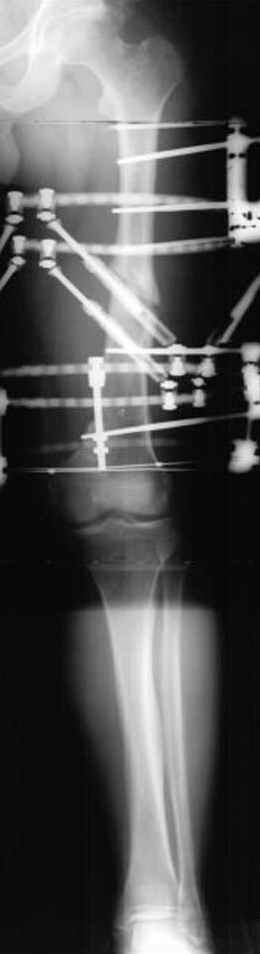

пластическая модель; и коррекция бедра аппаратом Илизарова.

хотя даже если бы и инфекция , то nail exchange с рассверливанием канала - вариант дебрайдмента) Я думаю, что последовательность развития событий:

Узкий к-м канал - тонкий гвоздь- усталостный перелом дистальных винтов - развитие нестабильности и как ее результат остеолиз вокруг гвоздя - деформация анатомической оси бедра. Похоже, что я понял почему аппарат, а не новый гвоздь:-)

ЕТ - Изначально костно-мозговой канал бедра был узкий, дальнейшее его рассверливание ещё больше скомпрометирует прочность бедра( латеральный кортекс дистального отломка уже истончен), приведет к дефекту наружной стенки - хотя это только мои догадки - хотелось бы знать мнение Джолдаса о выбранной тактике.